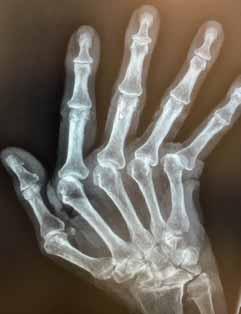

Hand met aangetaste gewrichten.

De MCP-gewrichten (knokkels) zijn vervangen en de vingers weer rechtgezet.